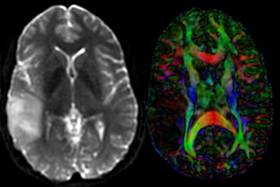

this is the fixed reference image. All images are aligned into this space lleft this is the T2 reference image, serves as target to the DTI baseline, but is itself aligned to the SPGR lleft this is the DTI tensor image, in the same orientation as the DTI Baseline

T2

moving image

DTI baseline+DTI tensor

This is a classic case of a multi-sequence MRI exam we wish to spatially align to the anatomical reference scan (T1-SPGR). The scan of interest is the DTI image to be aligned for surgical planning/reference. Unlike Case 27 this one does contain both a T1 and a T2 image. The T2 image being closer in contrast to the DWI/DTI baseline, it makes for the better registration reference. However the T1 contains the tissue contrast of interest.

Approach: we can use either T1 or T2 as the spatial reference. Ultimately we seek to overlay the DTI information onto the T1 image. But the T2 makes for a better registration reference because it matches better the DTI baseline contrast. Hence we will use the T2 as the reference and align the T1 to the T2 in a separate registration step. The typical DTI challenges are present here also: